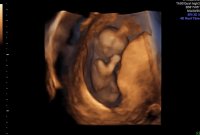

En liten gutt koser seg og vokser inni magen min.Vi fikk til og med se den lille hikke. Han klarte ikke ligge i ro et sekund, så godt å se at han er aktiv, sprellet med beina og vinket til oss! :D Ingen tegn til noe avvik eller kromosomfeil, så fantastisk godt å høre at lille ser frisk ut. CRL 9 cm :Heartblue sjekk siste bilde, der ser man rumpa og den lille saken som stikker ut:joyful: